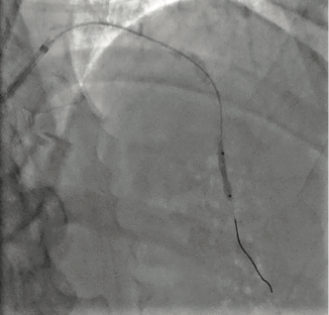

Quiz: Management of Calcified Lesions in Hospitals Without Surgical Backup

This quiz is based on an interview with B. Clay Sizemore, MD. Read "Management of Calcified Lesions in Hospitals Without Surgical Backup."